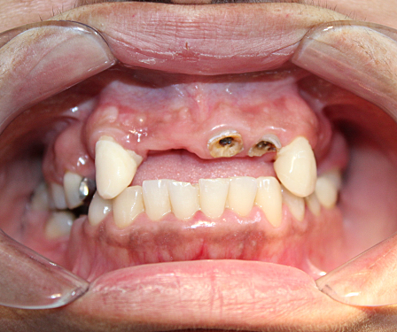

• FOTOS INTRAORALES

FOTOS INTRAORALES

Se realiza toma fotografica intraoral, donde se registra que el paciente se encuentra parcialmente edentulo tanto en carcada superior como inferior.

• ANALISIS DE SONRISA

ANALISIS DE SONRISA

La linea de la sonrisa no es valorable, esta linea se puede medir cuando hay organos dentarios anterosuperiores y anteroinferiores.

• FASE PROTESICA (COLOCACION DE PPR).

FASE PROTESICA (COLOCACION DE PPR).

Se confeccionan protésis parcial removible en ambas arcadas para sustituir los OD. 1.1, 1.2,1.6 y 2.1, 2.2, 2.4, 2.5, 2.6, 3.7, 4.5, 4.6, 4.7. se realizan las pruebas necesarias para lograr la adapatación, soporte y retención adecuada, con el fin de lograr la adecuada altura de la dimensión vertical. asi como la colocación de coronas libres de metal en OD. 1.3, 2.3, y 3.6. Quedando rehabiltado el paciente en su totalidad.